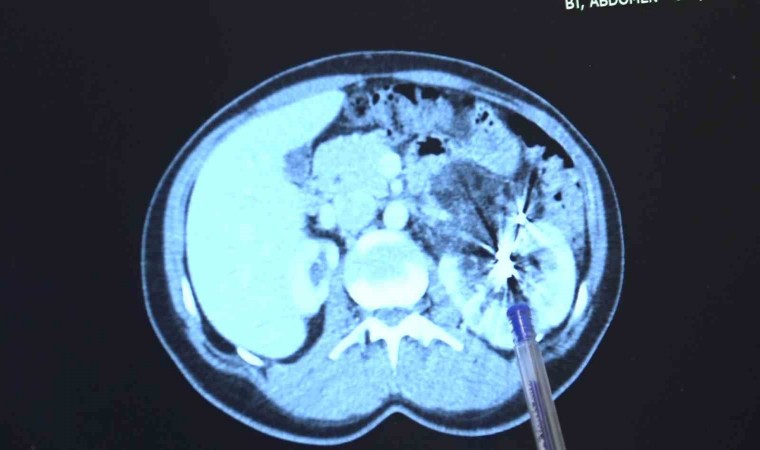

Zorlu bir ameliyatı başarıyla tamamlayan Bursa Medicana Hastanesi Üroloji Uzmanı Doç. Dr. Ahmet Şahan, hastanın durumunun şuan iyi olduğunu belirterek, “Nurcan Hanım 35 yaşında bize İzmir’den geldi. Doğuştan tek böbrekli bir böbreği küçük olduğu için işlevsiz durumda. Sağlam böbreğinde ise 2016’da tanısı konmuş giderek büyüyen iyi huylu "anjiomyolipomu" denilen 12 santimetre boyutunda bir kitlesi var. Bu kitle artık böbreğin damarlarını içerisine almış komplike bir kitle durumunda. Hastaya iki kez anjioembolizasyon tedavisi uygulanmış fakat başarısız olduğu için kitle büyümeye devam etmiş. Kadınlarda 4 santimetreden büyük anjiomyolipomular kendiliğinden kanayarak yaşamı tehlike altına attığı için bu kitlelerin alınması gerekiyor. Tek böbrekli olunan durumlarda böbreğin tamamen alınması durumu da söz konusu olabiliyor. Bu riske girmemek için çoğu merkez de embolizasyona başvurmuş. Hasta bize geldiğinde bu işi yapabileceğimizi söyledik. 2 saat süren kapalı bir ameliyatla kitleyi tamamen çıkardık ve hastamızı 3 gün içerisinde taburcu ettik. Hastamızın değerli şuan iyi durumda. Hastamızı diyalizden kurtarıp kapalı bir ameliyatla sağlığına kavuşturabildiğimiz için çok mutluyuz” dedi.